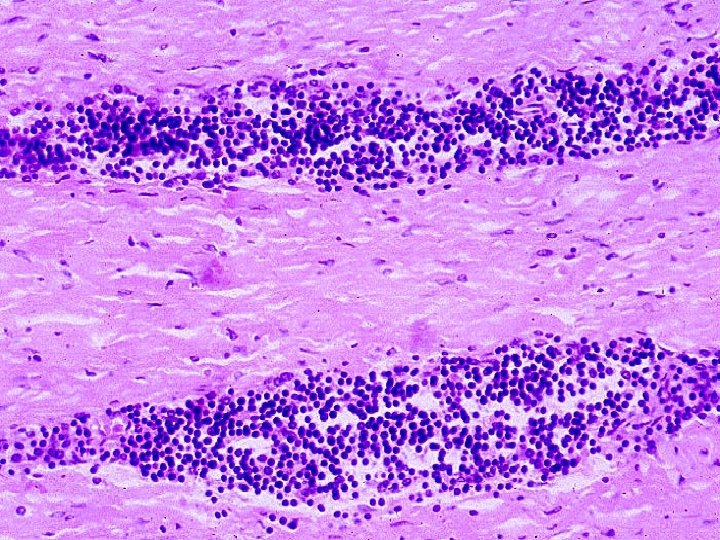

CHRONIC NON-SPECIFIC (NONGRANULOMATOUS) INFLAMMATION �It is the continuation of a partially successful acute inflammation & reaction to persistent extracellular bacteria �Histologically characterized by structureless unorganized diffuse infiltration of tissues by PMN’s and mononuclear cells

HISTOLOGICAL CHARACTERISTICS � Infiltration with mononuclear cells (eg. macrophages, lymphocytes and plasma cells) due to persistent reaction to injury � Tissue destruction induced by persistent agent or inflammatory cells � Attempts at healing by connective tissue replacement of damaged tissue with angiogenesis and fibrosis